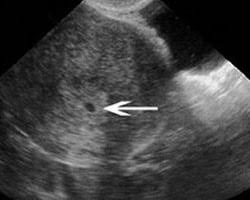

Gravidez Semana A Semana Nas Fotos De Ultrassom Gravidez Semana A Semana 2 Semanas De Gravidez 6 Semanas De Gravidez